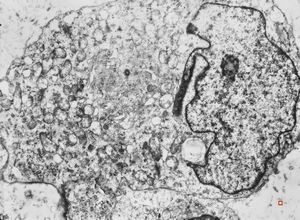

Giardia (Lamblia) intestinalis